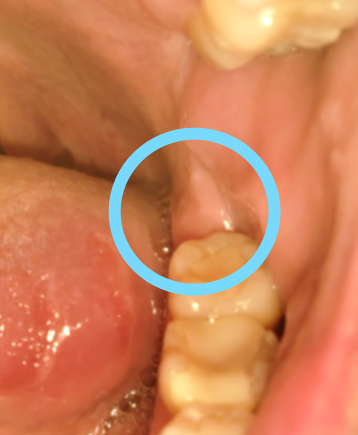

抜歯をしてから、今は8か月ほど経過しました。

現在のお口の状況はこんな感じです!

しっかりと組織が再生されています(*^_^*)よかったよかった!